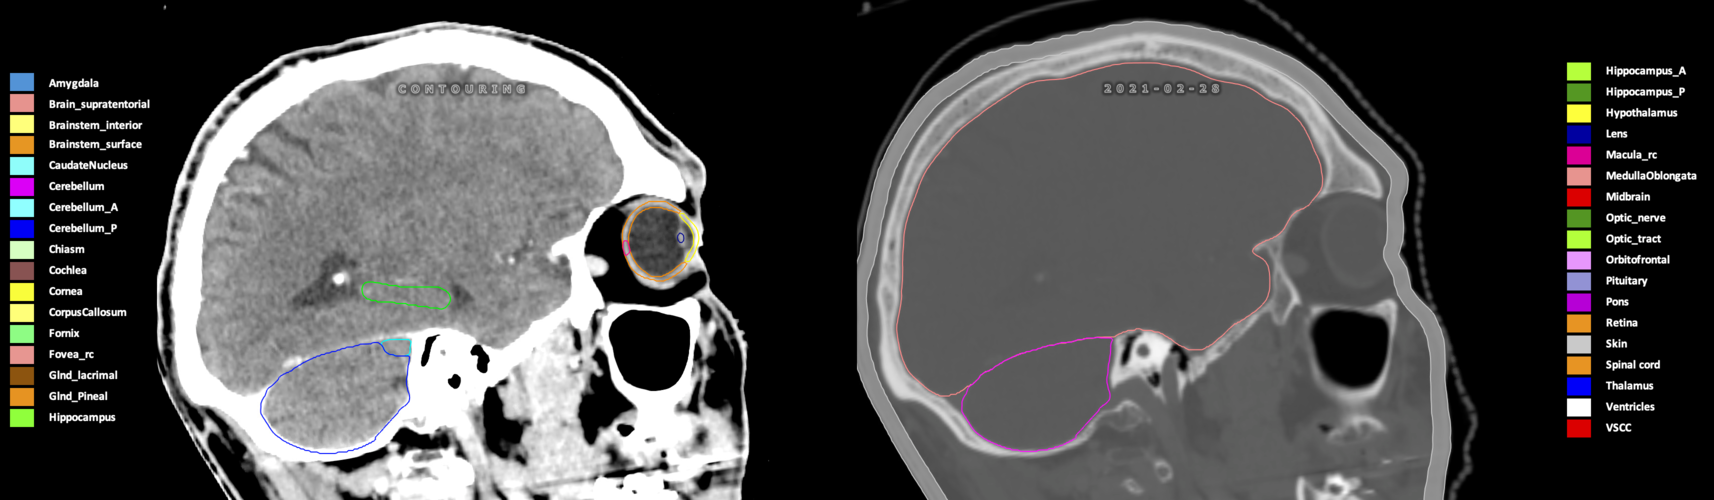

Included are all OARs known to be relevant for radiation-induced toxicity in neuro-oncology: brain, brainstem (midbrain, pons, medulla oblongata), chiasm, cerebellum (anterior & posterior), cochlea, cornea, hippocampus (anterior & posterior), hypothalamus, lens, lacrimal gland, optic nerve, pituitary, skin, and vestibular & semicircular canals. To further facilitate research on cognition, vision and radiological changes after irradiation of the brain, potential clinically-relevant OARs are included: amygdala, caudate nucleus, cerebellum (anterior & posterior), corpus callosum, fornix, macula, optic tract, orbitofrontal cortex, periventricular space (PVS), pineal gland, and thalamus.

Three-dimensional delineation of the 25 consensus OARs for neuro-oncology are shown on CT (WW/WL 120/40, 3000/600), 3T MR images, (T1Gd, T2FLAIR 1mm) and 7T MR (MP2RAGE 0.7 mm). All are presented in transversal, sagittal and coronal view.